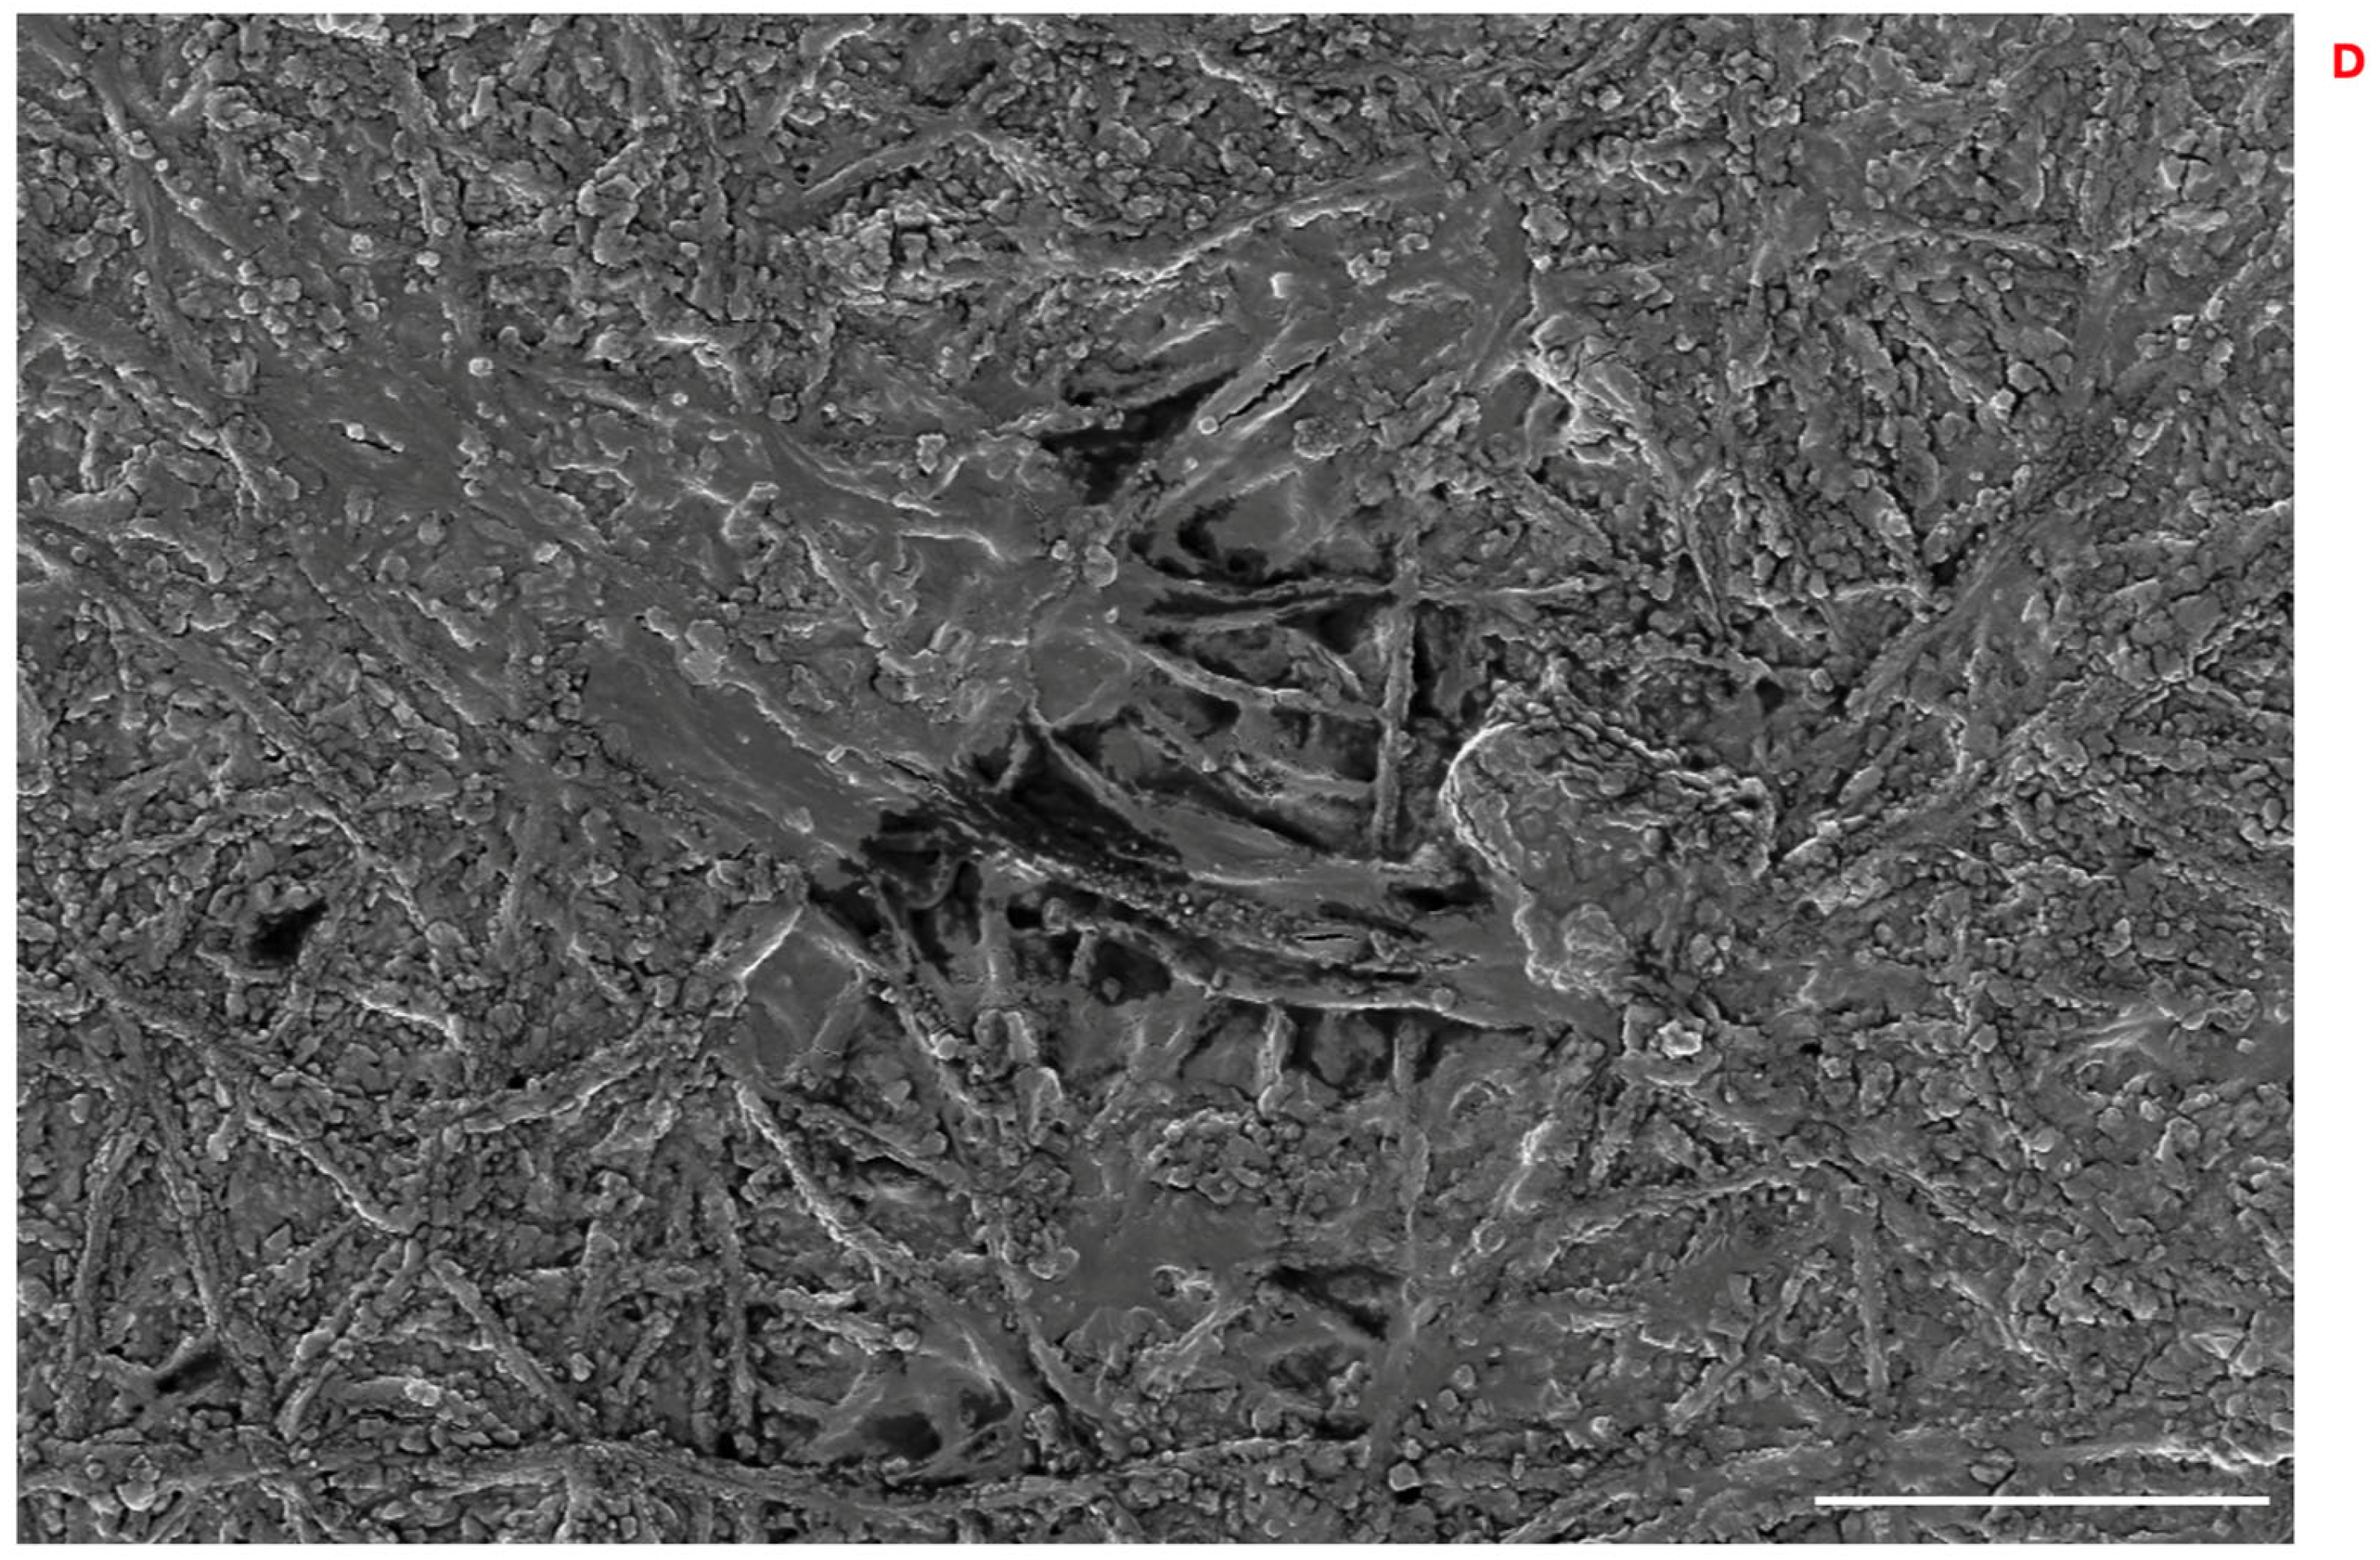

3.9. Proliferation of 3T3 Swiss Fibroblasts and HFs on PLA Scaffolds and DEX Intracellular Concentrations